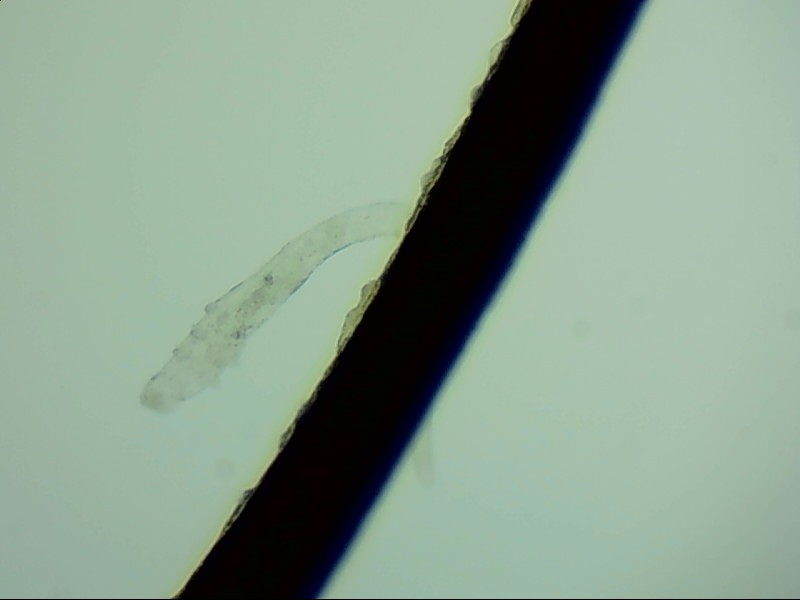

眼睛里的蛔蟲(chóng)

蛔蟲(chóng)是我們聽(tīng)聞最多的一種寄生蟲(chóng),它的出現(xiàn)往往帶著腸道、發(fā)育不良等字眼。但誰(shuí)能想到,蛔蟲(chóng)不但生活在腸道里,它還會(huì)在器官中移動(dòng),甚至進(jìn)入眼睛。